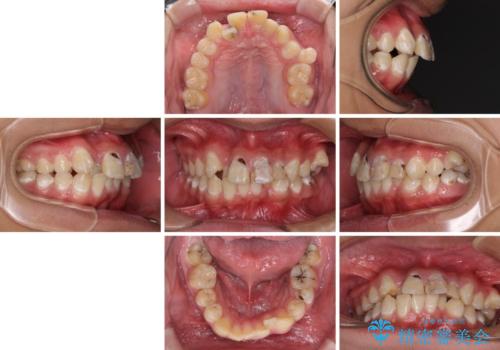

前歯のデコボコとむし歯だらけの歯列 矯正治療と虫歯治療

- 10代男性(高校生)

- 治療期間

- 2年6ヶ月

- むし歯が多く、歯並びも悪いとのことで、以前通院されていたご家族の紹介で来院された患者様です。

口腔内に無頓着であったため、まずはしっかりと歯磨きトレーニングを行い、必要な虫歯治療を行いました。

矯正治療は、むし歯が酷く抜歯が望ましい歯を1本抜歯して、ワイヤー装置にて整えることとしました。

矯正治療後は上顎前歯4本をオールセラミッククラウンにて補綴治療を行うこととしました。

- 治療費の目安: 150万円(税込)費用は治療当時の料金となります